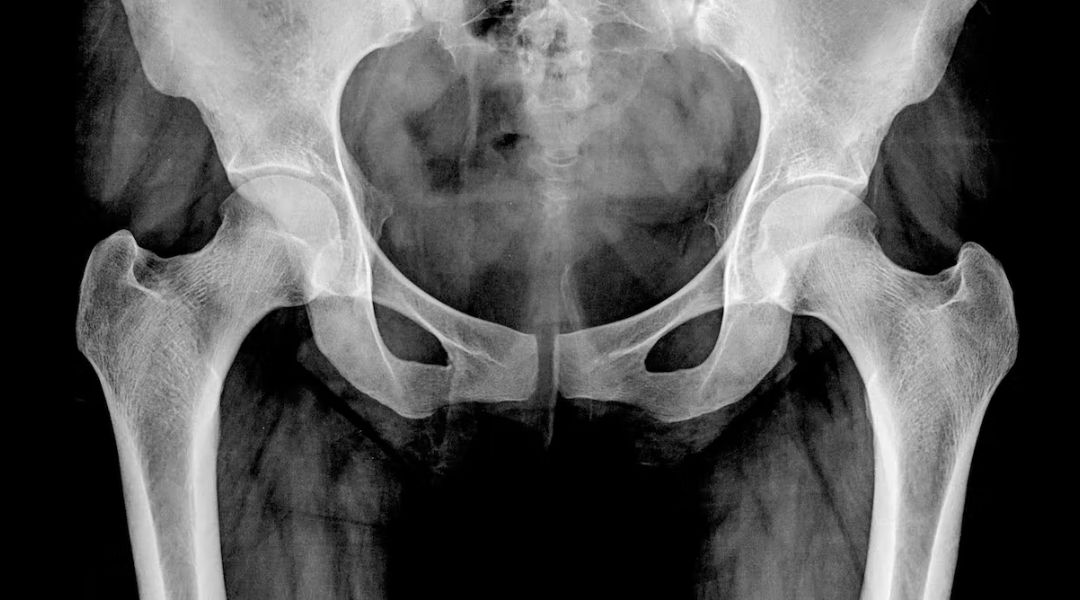

Es lo que les pasa a quienes padecen osteoporosis, que literalmente significa “hueso poroso”. La enfermedad se caracteriza por la reducción de la masa ósea y afecta al 30 % de las mujeres mayores de 50 años y al 8 % de los hombres.

La fragilidad ósea que acompaña a la osteoporosis reduce la calidad de vida de las personas que la padecen y se asocia con altas tasas de morbilidad y mortalidad. Además, en numerosas ocasiones se convierte en una enfermedad discapacitante.